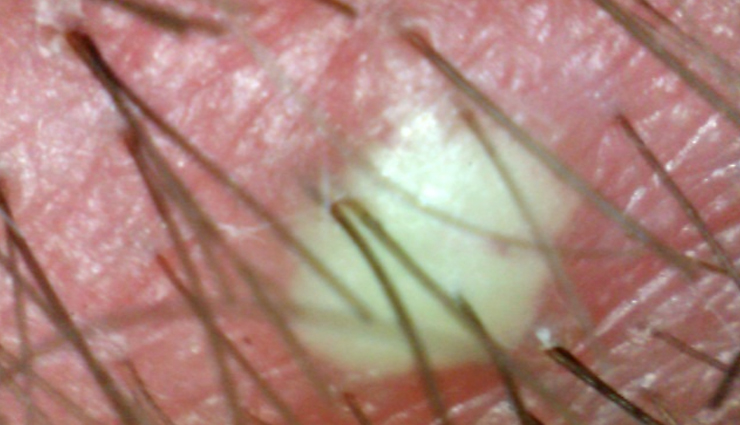

# Scalp Folliculitis

This chronic inflammatory condition directly impacts hair follicles, resulting in yellowish-white scabs on the scalp.

# White/Yellow Scabs

Excessive use of thick conditioners, ointments, lotions, or hair cream can trap moisture within scabs, causing them to appear white. Yellow scabs indicate the presence of infectious pus, leading to the formation of sores.